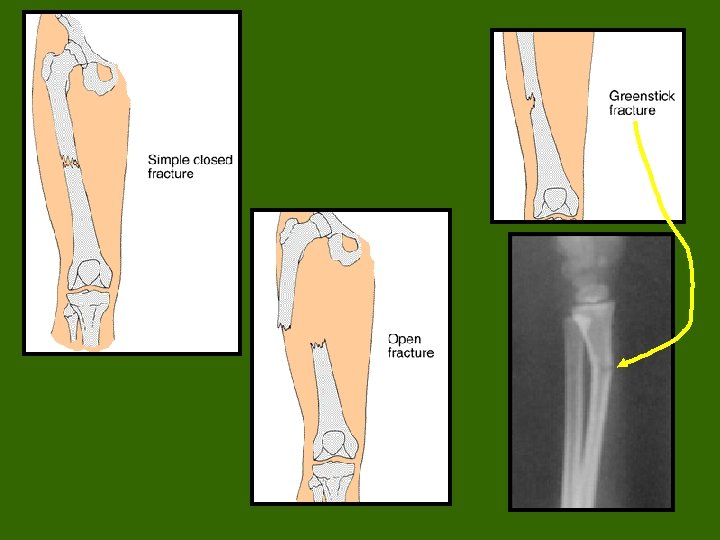

Fractures • Despite its mineral strength, bone may crack or even break if subjected to extreme loads, sudden impacts, or stresses from unusual directions. – The damage produced constitutes a fracture. • The proper healing of a fracture depends on whether or not, the blood supply and cellular components of the periosteum and endosteum survive.

Fracture Types • Fractures are often classified according to the position of the bone ends after the break: Open (compound) bone ends penetrate the skin. Closed (simple) bone ends don’t penetrate the skin. Comminuted bone fragments into 3 or more pieces. bones). Common in the elderly (brittle Greenstick bone breaks incompletely. One side bent, children collagen and are one side broken. Common in whose bone contains more less mineralized. Spiral ragged break caused by excessive twisting forces. Sports injury/Injury of abuse. Impacted one bone fragment is driven into the

Types of Fractures